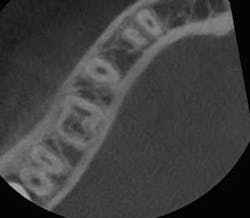

I offer the four clinical examples below to help you distinguish between internal and external resorption.- The outline of the canal in No. 24 is easily seen through the lesion, unaltered, and appearance is slightly ragged and irregular (figure 5).

- Diagnosis given to the patient at the time lesion was first noticed: internal resorption. As you can see, a root canal was completed, but no changes noted to the lesion. Patient continued to have discomfort post root canal therapy (figure 6).

- Reassessment: external resorption confirmed by a 3-D scan. Tooth was recommended for removal and an implant was placed.